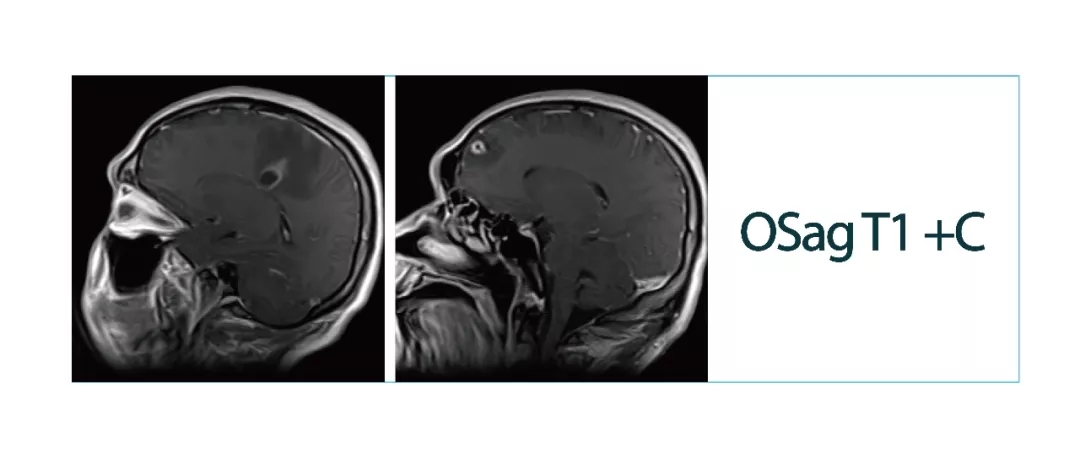

【朗润影像档案】磁共振影像病例分享(编号20180413)